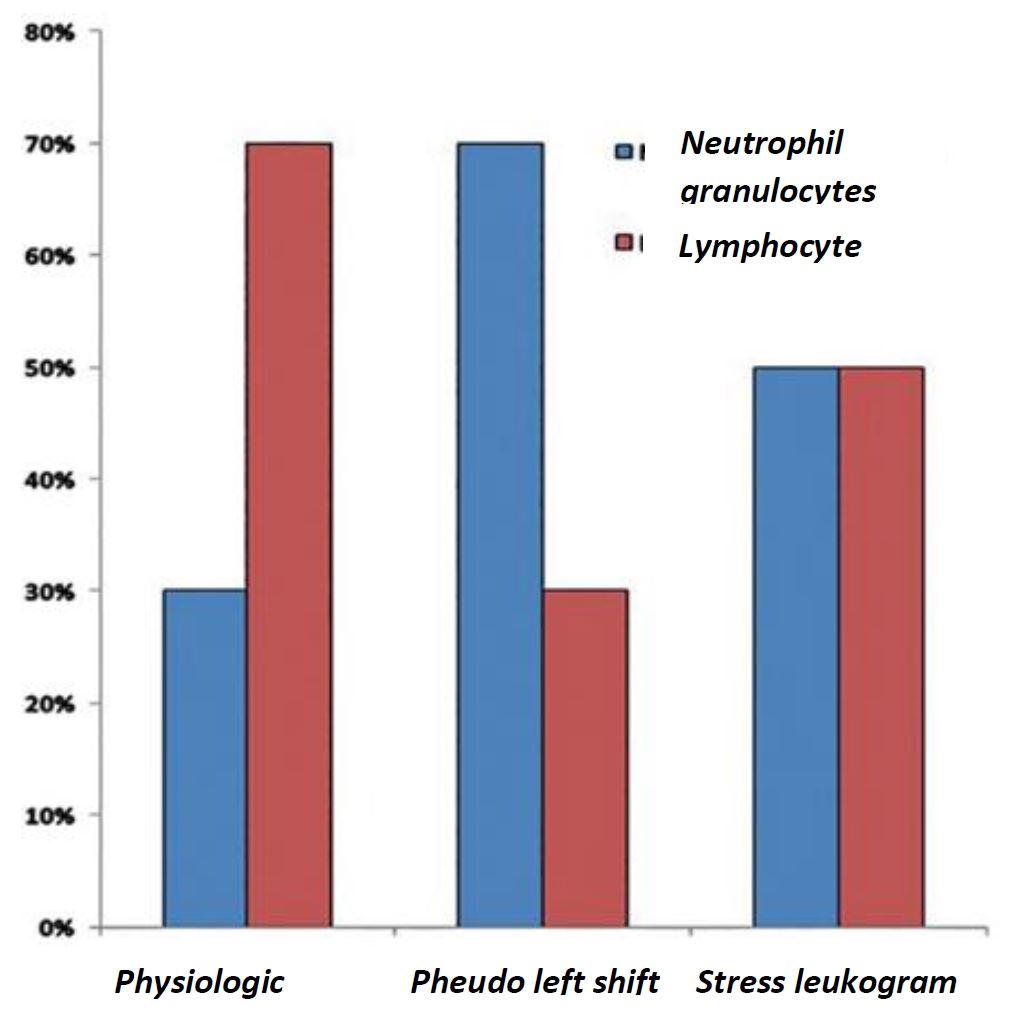

In contrast to dogs and cats, guinea pigs have a lymphocytic blood count. Physiologically, more lymphocytes than neutrophil granulocytes circulate in the peripheral blood. By acute bacterial infections or inflammation, a so-called “pseudo left shift” occurs – a shift from lymphocytic to granulocytic blood count. In this case, a marked leukocytosis as well as the presence of band neutrophils are, compared to other species, rarely seen. By the so-called “stress leukogram” are lymphocytes and granulocytes almost equally distributed.

- Fig. 3: Distribution of leukocytes